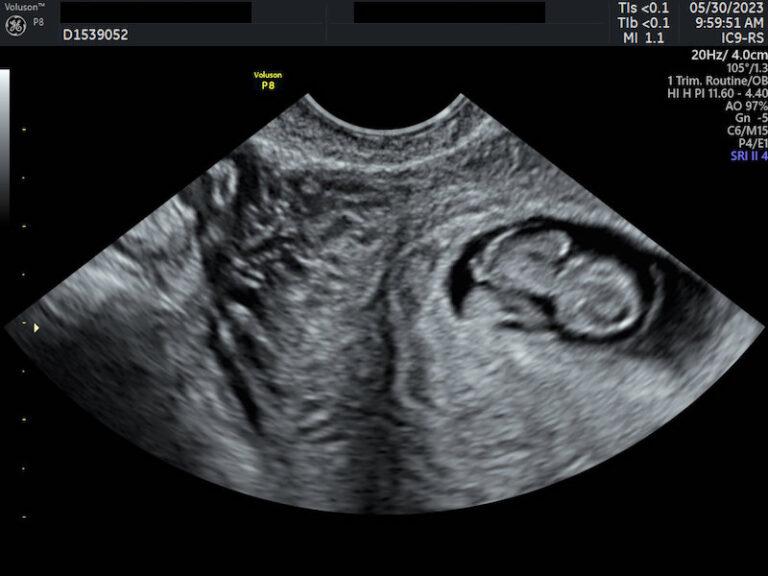

So happy to see this!! 🌈🙏🏼 Baby 3 & first after a miscarriage. Next What Do You See On Ultrasound After Miscarriage Most of the tissue passes within 2 to 4 hours after the cramping and bleeding start. You will be offered 2 routine ultrasound scans during pregnancy: If the pattern of changes in your hcg level. At 10 to 14 weeks (often called the dating scan) and between 18 and 21 weeks. In some types of miscarriage, you might not have. What Do You See On Ultrasound After Miscarriage.